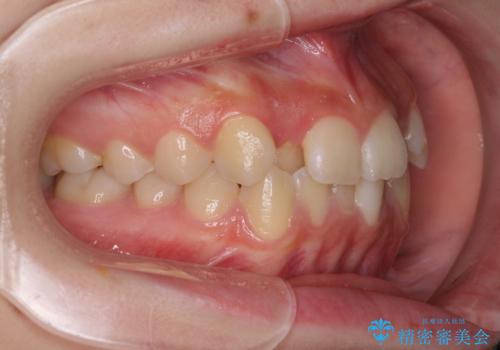

前歯のクロスバイト メタル装置での矯正治療

- 前歯のクロスバイトを気にして来院された患者様です。

前歯の叢生を解消するスペースを獲得するために上顎左右の親知らずを抜歯し、メタルブラケットにて矯正治療を行うこととしました。

当初は1年半程度の治療期間を想定していましたが、上下の正中を合わせていく過程で奥歯の咬みにくさが続いてしまい、2年以上の治療期間を要することとなりました。